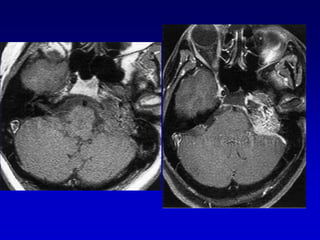

GLOMUS YUGULAR(paraganglioma)Erosion de la espina yugularInvasion hacia la caja timpánica

Caso 2TAC-RM

Caso 3TAC RM ANGIO